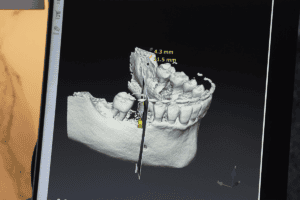

Dental implants have revolutionised the way people address missing teeth, offering a permanent, natural-looking solution that can restore both function and dental health.

However,

Choosing to undergo dental implant surgery, particularly the All-on-4 procedure, is a significant decision. The procedure itself can have a positive impact which can improve

The dental industry continues to innovate, replacing outdated and uncomfortable dental devices with modern, effective solutions. One such advancement is the All-on-4 dental implant system—a